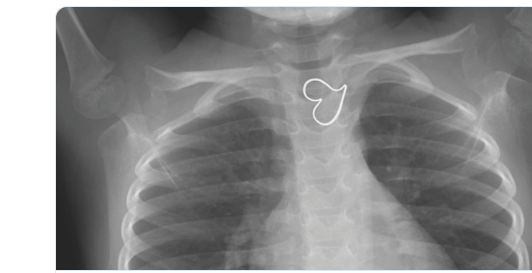

Image for Valentine’s Day

From NEJM twitter feed -an esophageal foreign body: